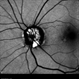

- CRAO, takayasu arteritis, calcified drusen

- Fundus fluorescein angiography image of a young girl with diagnosed Takayasu arteritis who presented with complains of diminished vision in both eyes. FFA shows complete absence of venous filling with segmented blood column secondary to CRAO with peripheral avascular area.